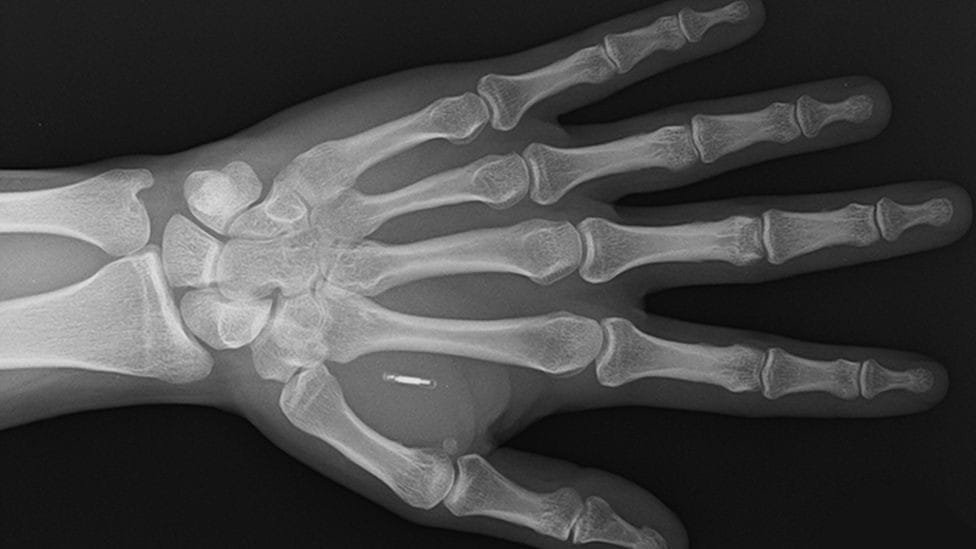

Patrick Paumen, bir mağaza veya restoranda ödeme yaparken etraftaki insanların dikkatini çekmeyi başarıyor. Bunun sebebi, 37 yaşındaki Paumen’in banka kartı ya da cep telefonu kullanmadan, yalnızca elini temassız kart okuyucusuna yaklaştırarak ödeme gerçekleştirmesi. BBC’nin haberine göre, “Kasiyerlerden aldığım tepkiler paha biçilemez” diyor Hollandalı güvenlik görevlisi Paumen. 2019 yılında, derisinin altına temassız bir ödeme mikroçipi enjekte ettirerek bu kolaylığı elde etti.

Paumen, mikroçipin yerleştirilme sürecini “Prosedür, birinin cildinizi çimdiklemesi kadar acıtıyor” şeklinde tanımlıyor. Sol elinin derisinin altındaki bu çip, bir ödeme makinesiyle yakın temasa geçtiğinde yanan ışığıyla kendini gösteriyor. Deri altına entegre edilen ödeme çipleri konusunda, İngiltere ve Polonya merkezli Walletmor firması, bunları satışa sunan ilk şirket olma özelliğini taşıyor. Kurucu ve CEO’su Wojtek Paprota, “İmplant, Rio’da bir içki, New York’ta bir kahve ya da Paris’te bir saç kesimi için – ya da yerel bakkalınızda ödeme yapmak için kullanılabilir. Yani temassız ödemenin kabul edildiği her yerde kullanılabilir” diye belirtiyor.

Walletmor’un çipi, bir gramdan daha hafif ve bir pirinç tanesinden biraz daha büyük boyutta. Çip, küçük bir mikroçip ve doğada türetilmiş bir malzeme olan biyopolimer içine yerleştirilmiş bir anten içeriyor. Paprota, bu teknolojinin tamamen güvenli olduğunu, yasal onay aldığını, implante edildikten hemen sonra çalışmaya başladığını ve sıkı bir şekilde vücutta kalacağını iddia ediyor. Ayrıca, bu çiplerin bir pil ya da başka bir güç kaynağına ihtiyaç duymadığını vurguluyor. Firma, şu anda 500’den fazla çip sattığını bildiriyor.